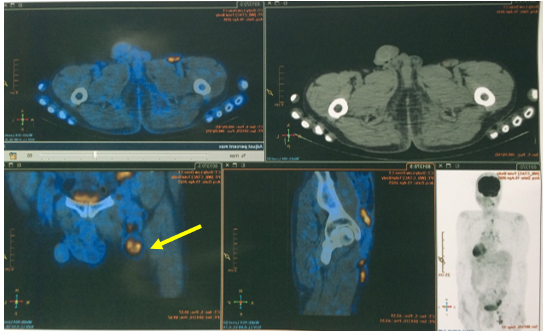

– PET/CT (Tháng 03/2025): Không thấy tổn thương tăng hấp thu FDG khu trú bất thường tại hạ họng. Hình ảnh hạch nhóm 1R, kích thước 12x15mm, tăng chuyển hóa glucose, khả năng do di căn. Đề nghị đối chiếu với mô bệnh học. Hình ảnh tổn thương giảm tỉ trọng kèm vôi hóa kích thước ~33x50x39mm, tăng chuyển hóa glucose ở hạ phân thuỳ VII gan, tương ứng với tổn thương gan đã nút mạch, theo dõi tiến triển. Hình ảnh nhiều hạch ở dọc theo động mạch chậu chung và chậu ngoài phải, bẹn phải, tăng chuyển hóa glucose. Đề nghị đối chiếu với mô bệnh học. Chưa phát hiện hình ảnh tăng hấp thu FDG bất thường, khu trú tại các vị trí khác trên xạ hình PET/CT toàn thân.

Hình 6: Hình ảnh hạch bẹn, kích thước 14x29mm, SUV max 8,9 (mũi tên vàng)